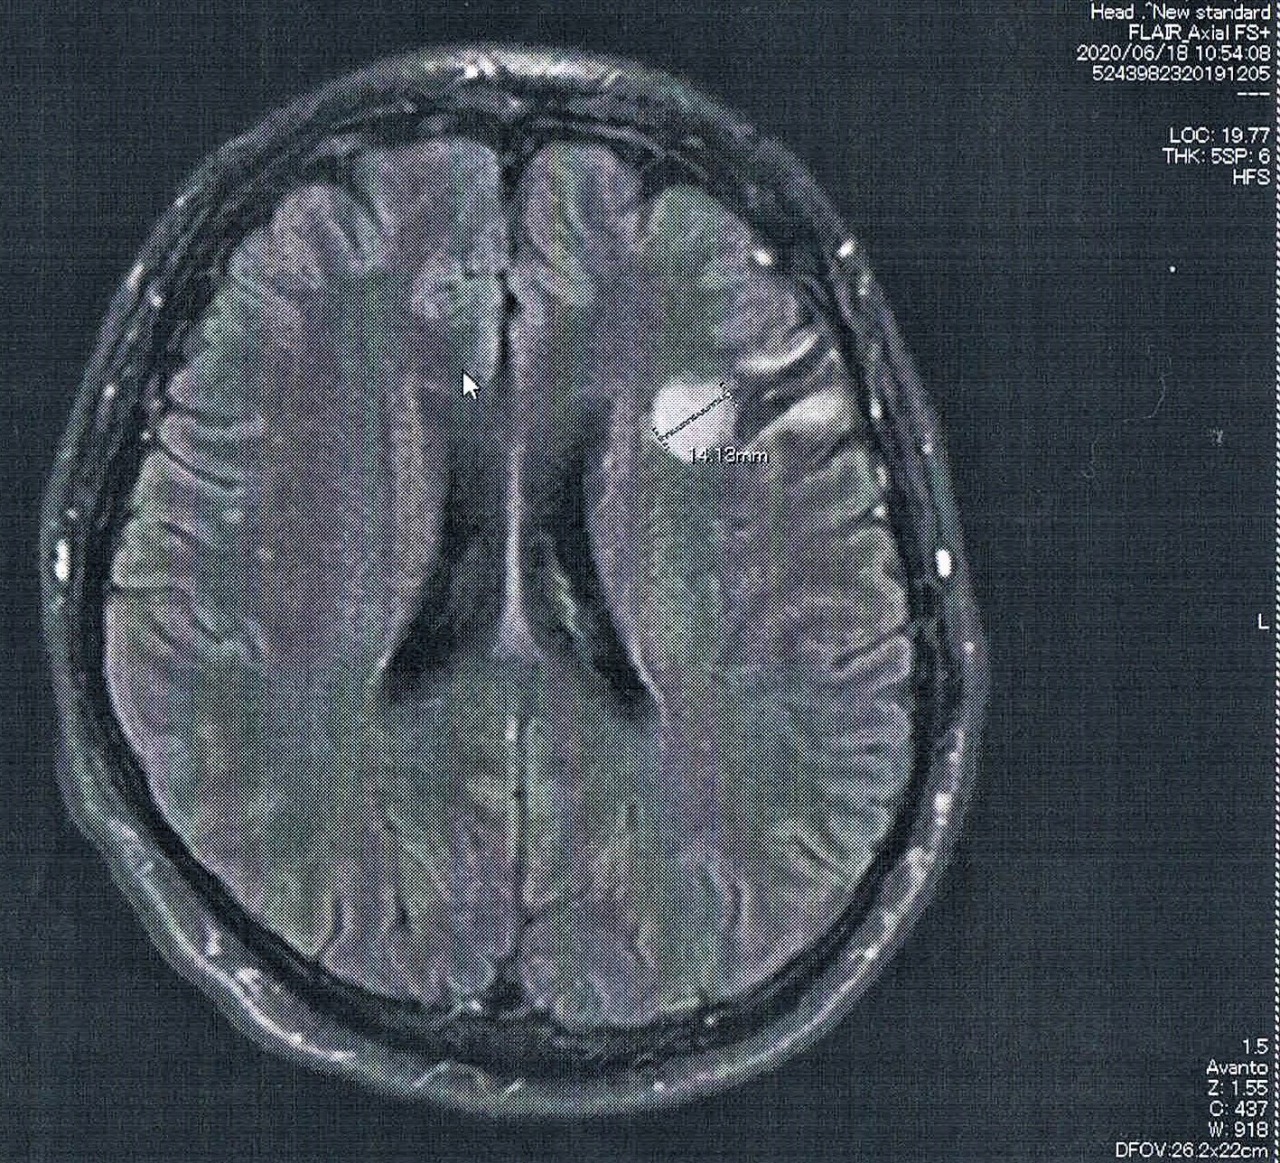

前回から造影剤を注射してMRI検査をすることになった。手術から6年が経過し、悪性転化しやすい腫瘍の種類(びまん性星細胞腫グレード2)であるとのことで念のため。

診断の結果は特に変化はなく問題なし。造影剤がしみ込んでいる箇所もないとのことで、悪性度は低い状態を保っているとのこと。